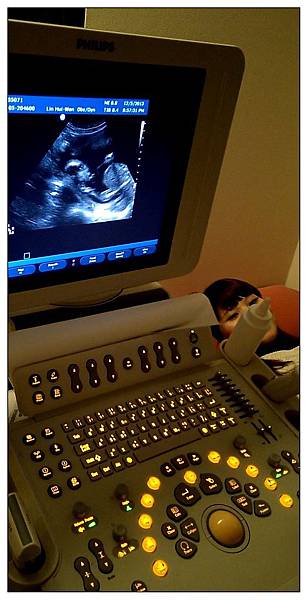

這次是第三次的正式產檢囉!!

林慧雯醫生也是很知名的婦產科女醫生~~~

20周的蔡小球因為身體器官都已經逐漸發展完成~~

所以醫生這次照超音波就照得很仔細~~除了胎心音之外

從頭檢查到眼睛、鼻子、手指頭、腳趾頭、脊椎、胃全部一一指出來給我們看